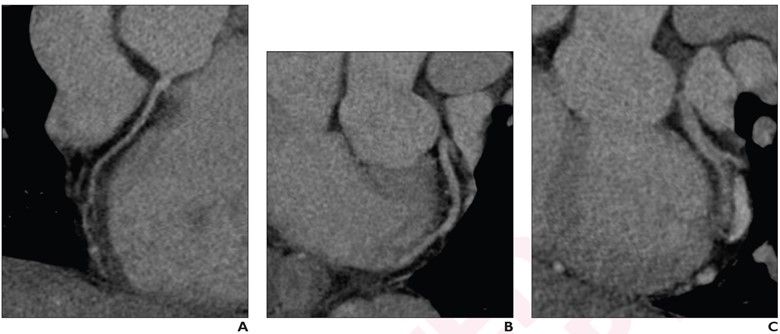

Recently published research revealed that coronary computed tomography angiography (CCTA) exams performed with dual-source CT were completed 22 minutes faster and had a nearly 28 percent higher frequency of good or excellent image quality in comparison to CCTA exams performed with single-source CT devices.

Derived from coronary computed tomography angiography (CCTA) images, a radiomics model demonstrated a 75 percent or greater area under the curve (AUC) in multiple test sets for identifying vulnerable plaque.